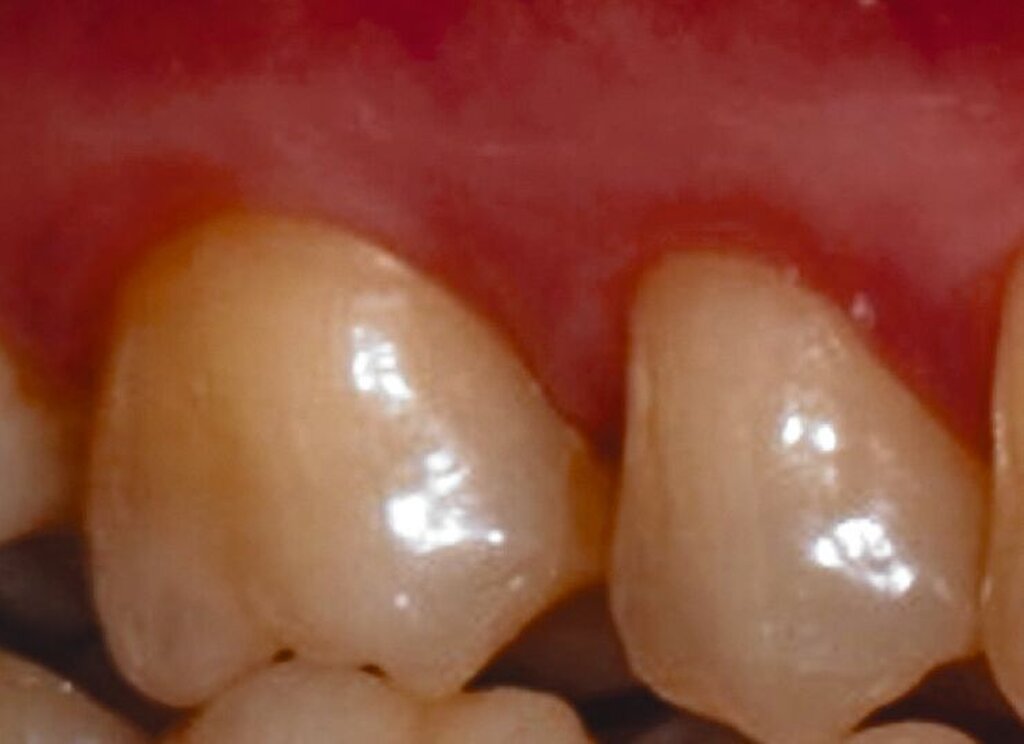

Fall 1 – einfach